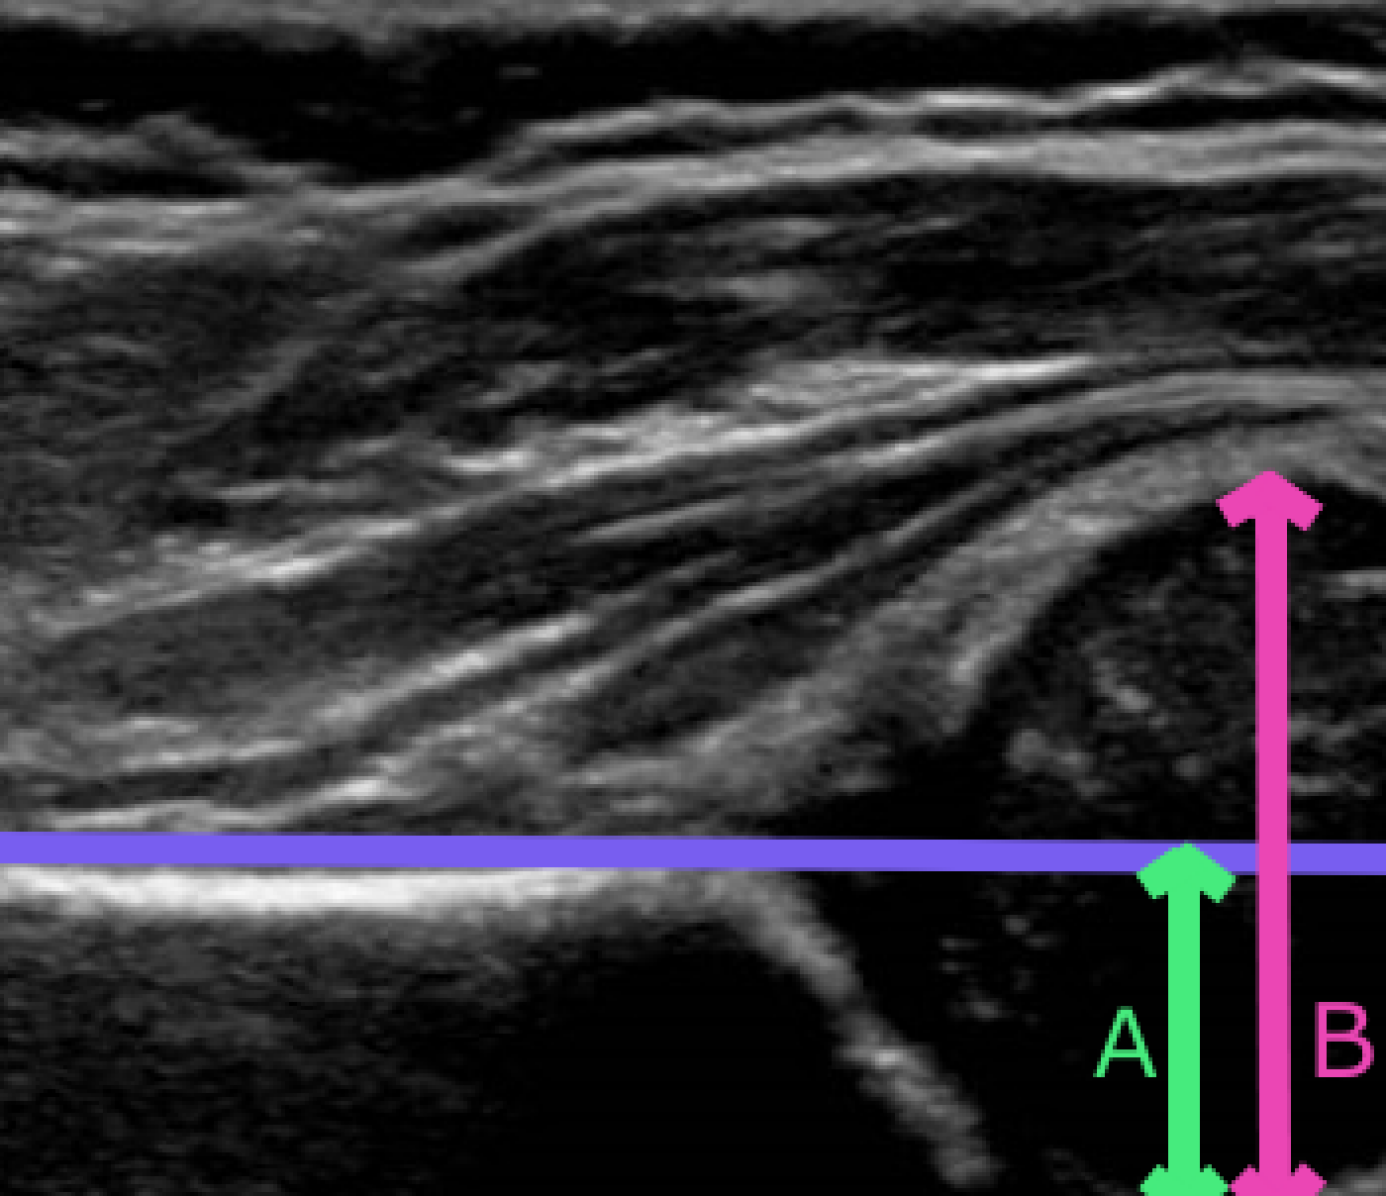

Ultrasound imaging is more sensitive (clinically) than a physical examination and is ideal for screening programmes as it is safe and portable [3]. The Femoral Head Coverage (FHC) method is used to provide objective evidence where a straight line is drawn extending along the upper edge of the ilium (Fig. 1) and the femoral head proportion on each side of the line is measured [4]. Clinically, a decision value of 50%percent5050\% coverage is used, with a larger percentage below the line (FHC>>50%) identified as healthy and a larger percentage above the line (FHC\leq50%) termed DDH [5].

State of the art literature for automatic DDH evaluation uses the Graf method [6, 7, 8]. However, this method has extremely high inter-operator variability and it only achieves approximately 85% agreement with clinicians. Our reproducible algorithm takes automated numerical measures of the FHC (AFHC) to classify the presence or absence of DDH. It does so by segmenting key anatomical structures from static 2D ultrasound images: ilium, femoral head and labrum (Fig. 1). Clinicians are able to identify these structures and diagnose by simply inspecting the scan (Gestalt laws) [9].

Fig. 1: (a) Static ultrasound of hip joint, annotated with femoral head, ilium and labrum. (b) Measurements required for FHC evaluation: FHC%=AB×100percentFHC𝐴𝐵100{\textsc{FHC}}\%=\frac{A}{B}{\times}100.